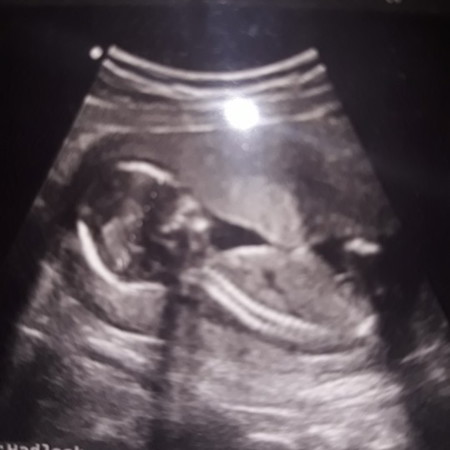

USG bayi seperti kesempitan

Bunda, td siang aku abis USG, usia 15 week, pas ku lihat2 hasilnya di rumah itu janinnya kok kayak kesempitan gitu ya? Apakah gmbar tsb menunjukan air ketuban yang sedikit? Td dokter cuma bilang sehat aja udah..

Jgn menyimpulkan sendiri bu. Jika kurang air ketuban pasti dokter bilang Perbanyak minum air putih Jika sempit janin tdk bisa bergerak sama sekali. Selama dokter bilang sehat InsyaAllah janin sehat

Ada2 aja bun, kan dokter yg lebih tau selama baik2 aja ya berarti aman